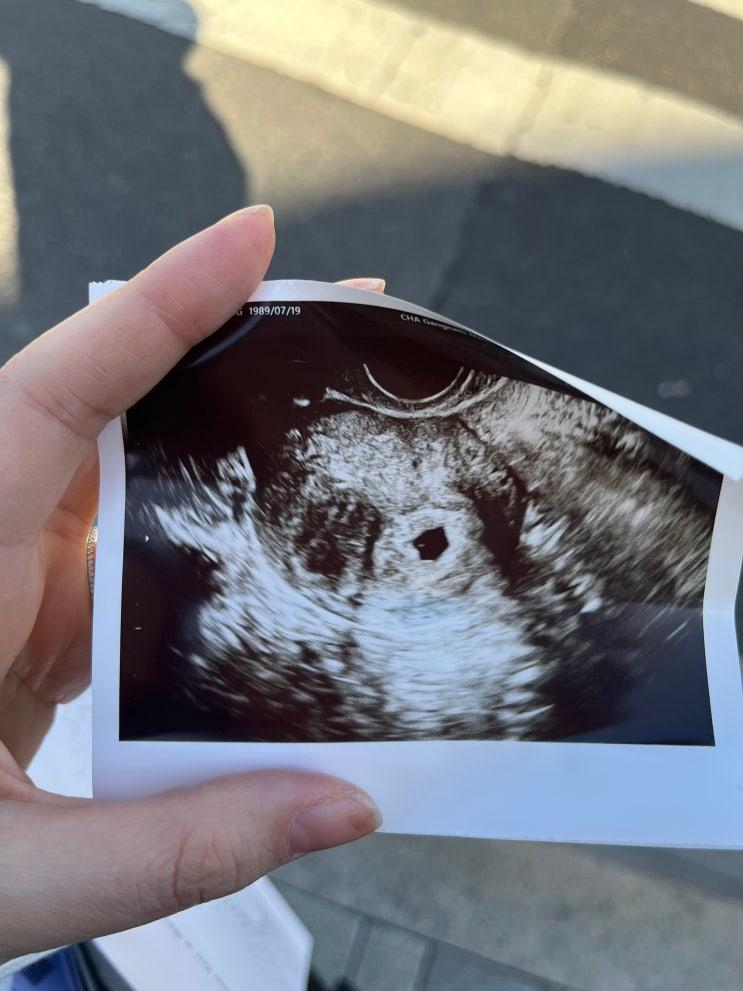

[5w,5d] 다이아몬드 링 발견, 뜻밖에 심장소리

갈색혈이 토요일부터 보였다. 월요일이 되니 거의 보이지 않아서 괜찮아지겠지 했지만 .. 수요일에 갑자기 ...